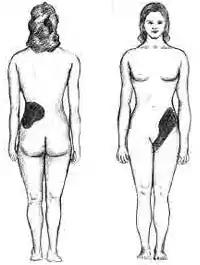

The hallmark of a stone that obstructs the ureter or renal pelvis is excruciating, intermittent pain that radiates from the flank to the groin or to the inner thigh.[14] This is due to the transfer of referred pain signals from the lower thoracic splanchnic nerves to the lumbar splanchnic nerves as the stone passes down from the kidney or proximal ureter to the distal ureter. This pain, known as renal colic, is often described as one of the strongest pain sensations known.[15] Renal colic caused by kidney stones is commonly accompanied by urinary urgency, restlessness, hematuria, sweating, nausea, and vomiting. It typically comes in waves lasting 20 to 60 minutes caused by peristaltic contractions of the ureter as it attempts to expel the stone.[14]

The embryological link between the urinary tract, the genital system, and the gastrointestinal tract is the basis of the radiation of pain to the gonads, as well as the nausea and vomiting that are also common in urolithiasis.[16] Postrenal azotemia and hydronephrosis can be observed following the obstruction of urine flow through one or both ureters.[17]

Pain in the lower-left quadrant can sometimes be confused with diverticulitis because the sigmoid colon overlaps the ureter, and the exact location of the pain may be difficult to isolate due to the proximity of these two structures.